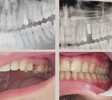

Implant tedavisi

Zirkonyum uygulamalar

Porselen uygulamaları